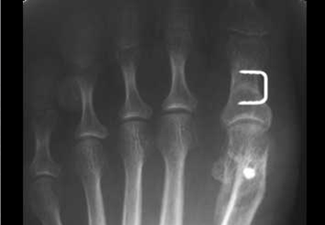

Desplazamiento clásico obtenido con la oesteotomía en chevron.

Osteosíntesis de la osteotomía con tornillo.